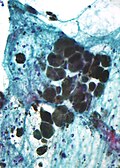

Images

- Granuloma cytology.jpg

Granuloma - cytology. (WC)

- Granulomatous inflammation -- intermed mag.jpg

GI - intermed. mag. (WC)

- Granulomatous inflammation -- high mag.jpg

GI - high mag. (WC)

- Granulomatous inflammation - alt -- high mag.jpg

- Granulomatous inflammation -- very high mag.jpg

GI - very high mag. (WC)